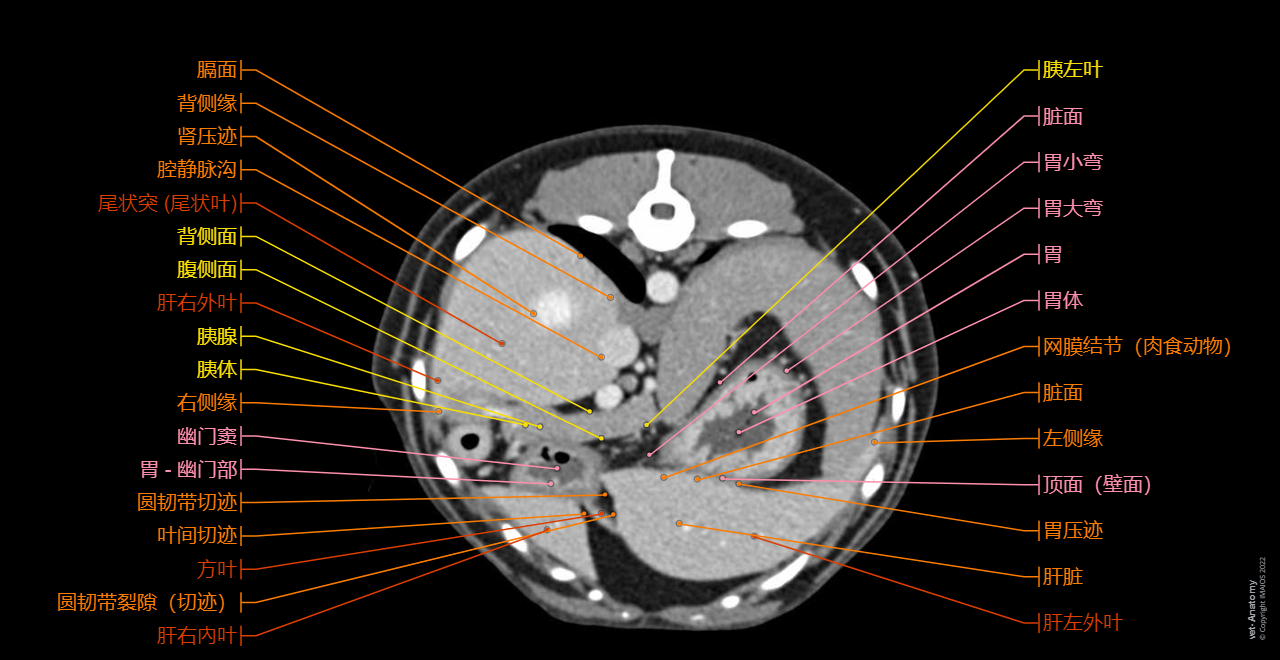

vet-Anatomy兽医图集的本模块是关于CT扫描的犬类腹部和骨盆。

CT图像来自一只健康的6岁阉割雄性犬。

在vet-Anatomy动物图集的此模块中,计算机断层扫描(CT)显示了标有解剖结构的犬科腹腔和骨盆横截面,并用3D图像显示犬科腹部。

CT图像存在3个平面方向(横向,矢状和背侧),并且使用两种对照方式(软组织/血管和骨骼)展现。本模块的末尾提供其他3D解剖图像,便于进一步了解犬科总体解剖结构,展示了骨骼、内脏(肝脏、脾脏、胰腺、消化道)、泌尿生殖系统、动脉、全身静脉系统(主要是尾腔静脉及其分支)、门静脉系统、肌肉和表面解剖的三维容积透视图。

毕业于欧洲兽医诊断影像学学会的Susanne AEB Boroffka博士(荷兰乌得勒支)对健康的6岁雄性阉割犬(拉布拉多猎犬)注射碘化造影剂并完成计算机断层扫描。

三维容积透视图是由Antoine Micheau博士在GE ADW上使用相同的CT医学影像成像数据而创建。

放射科医生(法国蒙彼利埃)Antoine Micheau博士和放射科医生(法国蒙彼利埃)Denis Hoa博士完成了图像显示、解剖标记和解剖释义工作。

Cross-sectional labeled anatomy of the abdomen and male pelvis of the dog on CT imaging (liver, hepatic segmentation, pancreas, biliary tract, digestive tract, small and large intestine, kidney, bladder, genital organs, peritoneum)